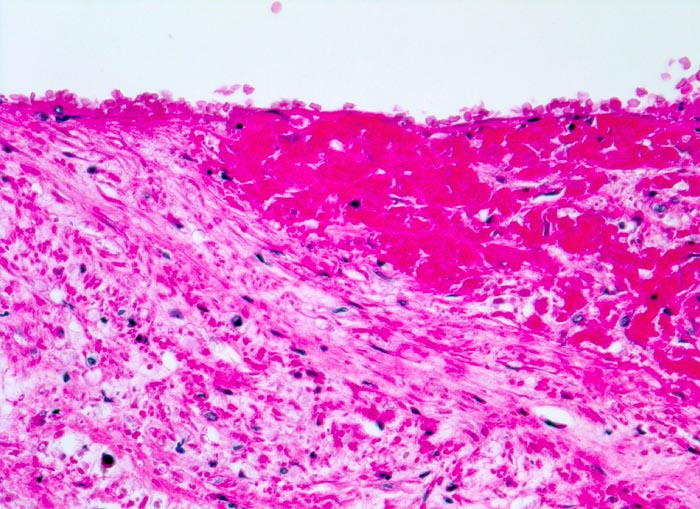

PathoPic – image database / PathoPic ID 4561 - Venenthrombose in Organisation

Venenthrombose in Organisation

Ausläufer einer älteren Thrombose. Das Fibrin der Thrombose ist bereits in die Venenwand inkorporiert. Der organisierte Thrombusanteil wird bedeckt von neugebildetem Endothel.

Todesursache: Multiple ältere periphere und frische parazentrale Lungenembolien.

Metastasierendes Tumorleiden. Der Patient wird tot im Bett aufgefunden.